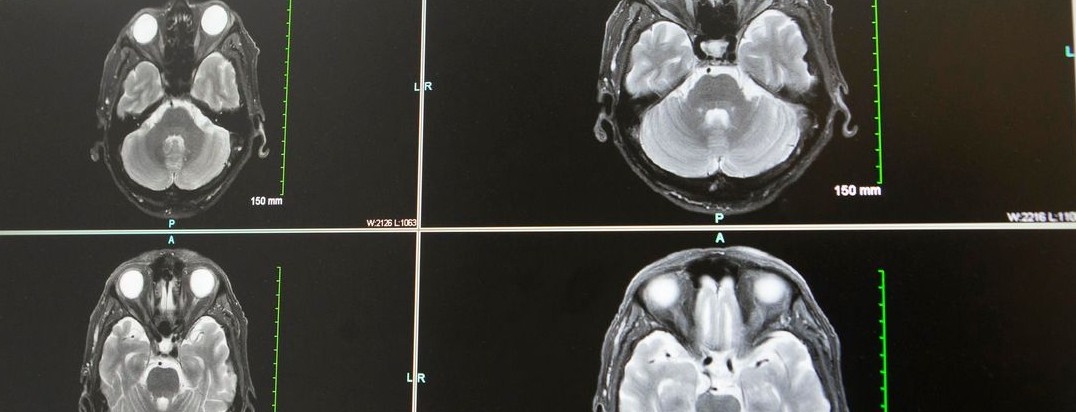

Intracerebral hemorrhage (ICH) accounts for only 10% of all strokes, but it is likely the deadliest. There is a need for more research to determine best practices to manage acute hypertensive ICH.

Featured photo at top of brain scans. Photo courtesy of Joseph Broderick.